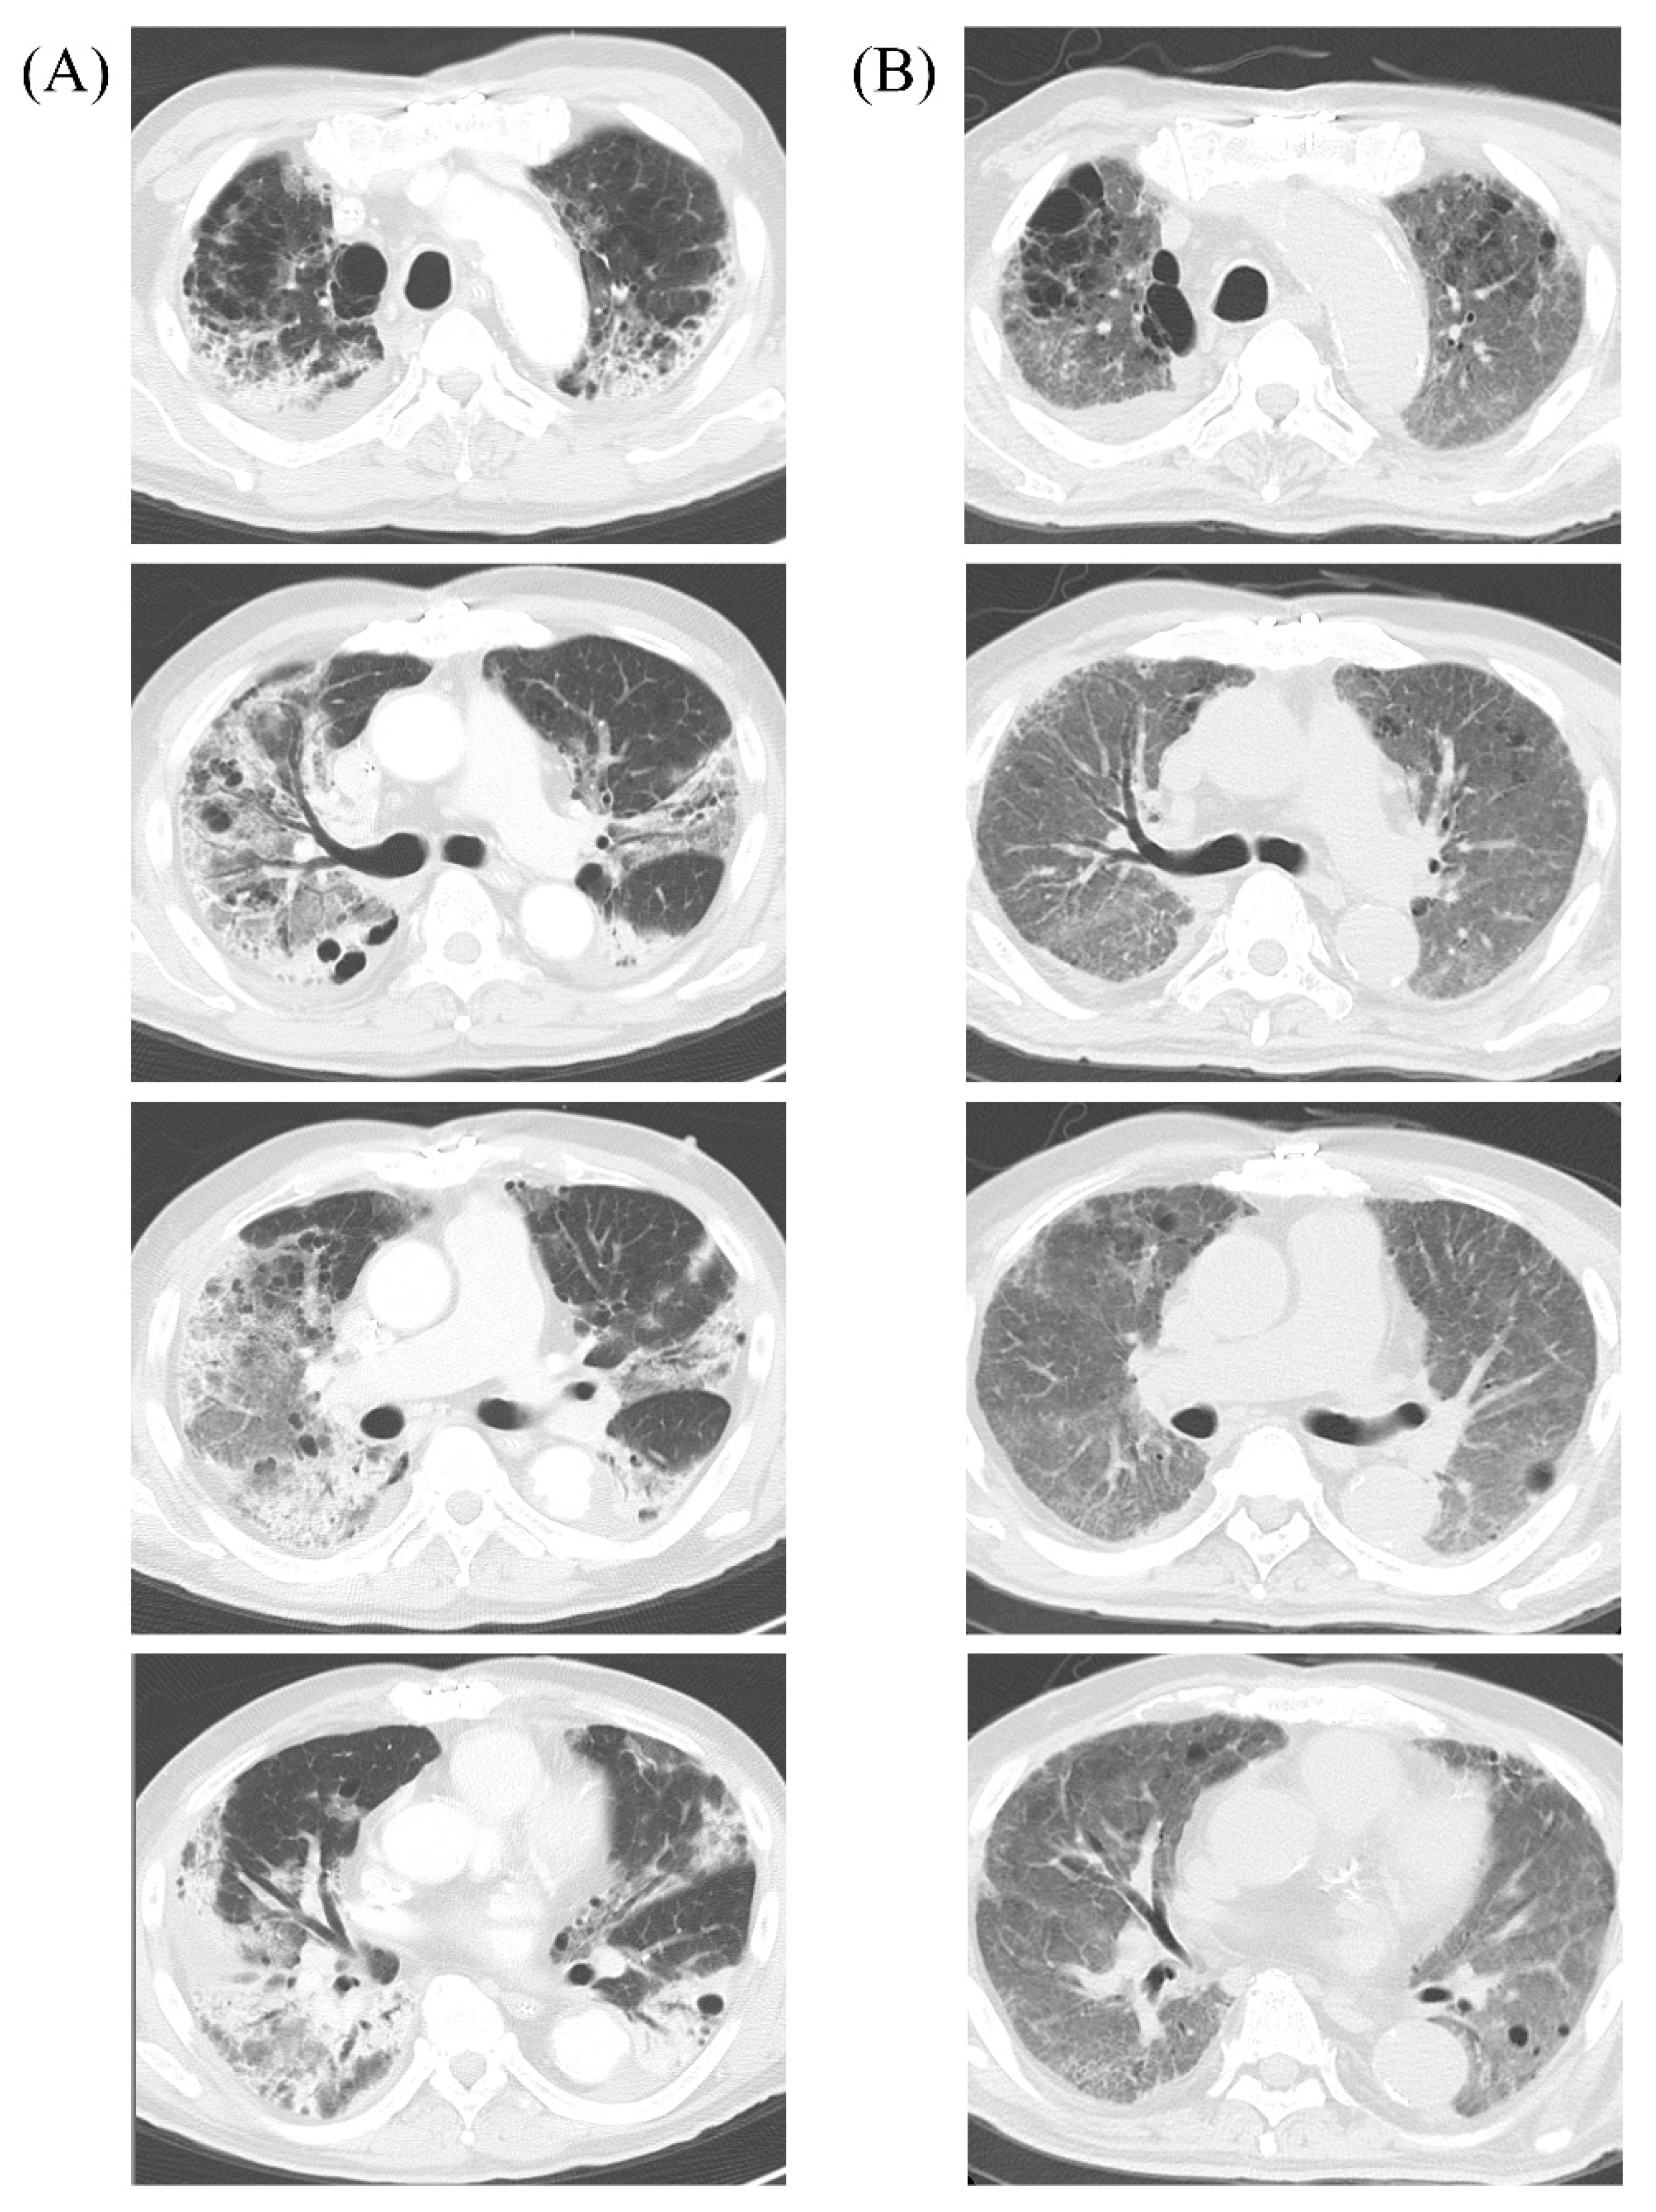

| MIC Value (µg/mL) and Interpretation | ||||||

|---|---|---|---|---|---|---|

| Organism | Klebsiella aerogenes (KE-1) | Klebsiella aerogenes (KE-2) | Citrobacter koseri | Pseudomonas aeruginosa | MDRP | |

| Source | Blood | Drainage Culture | Sputum | Sputum | Sputum | |

| Antibiotics | Ampicillin | >16 R | >16 R | >16 R | ||

| Ampicillin-sulbactum | >16 R | >16 R | ≤4 S | |||

| Amoxicillin-clavulanate | >16 R | >16 R | ≤8 S | |||

| Piperacillin | 16 S | 64 I | >64 R | 16 S | 32 I | |

| Piperacillin-tazobactam | 8 S | 16 S | 8 S | 8 S | 32 I | |

| Cefazolin | >16 R | >16 R | ≤1 S | |||

| Cefmetazole | >32 R | >32 R | ≤4 S | |||

| Ceftriaxone | ≤0.5 S | >2 R | ≤0.5 S | |||

| Ceftazidime | >8 R | >8 R | ≤1 S | 4 S | >16 R | |

| Cefepime | ≤1 S | 8 S | ≤1 S | 8 S | >16 R | |

| Imipenem | 2 I | >2 R | ≤0.5 S | 1 S | >8 R | |

| Meropenem | ≤0.25 S | >2 R | ≤0.25 S | ≤0.5 S | >8 R | |

| Aztreonam | ≤1 S | >8 R | ≤1 S | >16 R | >16 R | |

| Amikacin | ≤8 S | ≤8 S | ≤8 S | ≤4 S | 32 I | |

| Gentamicin | ≤2 S | ≤2 S | ≤2 S | 2 S | 8 I | |

| Tobracin | ≤1 S | 4 S | ||||

| Minocycline | >8 R | >8 R | 4 S | |||

| Ciprofloxacin | <0.25 S | >2 R | <0.5 S | 0.5 S | >4 R | |

| Levofloxacin | 1 S | >4 R | ≤0.12 S | 2 S | >8 R | |

| Fosfomycin | ≤4 S | >16 R | ≤4 S | >16 R | >16 R | |

| Trimethoprim-sulfamethoxazole | ≤40 S | ≤40 S | ≤40 S | |||